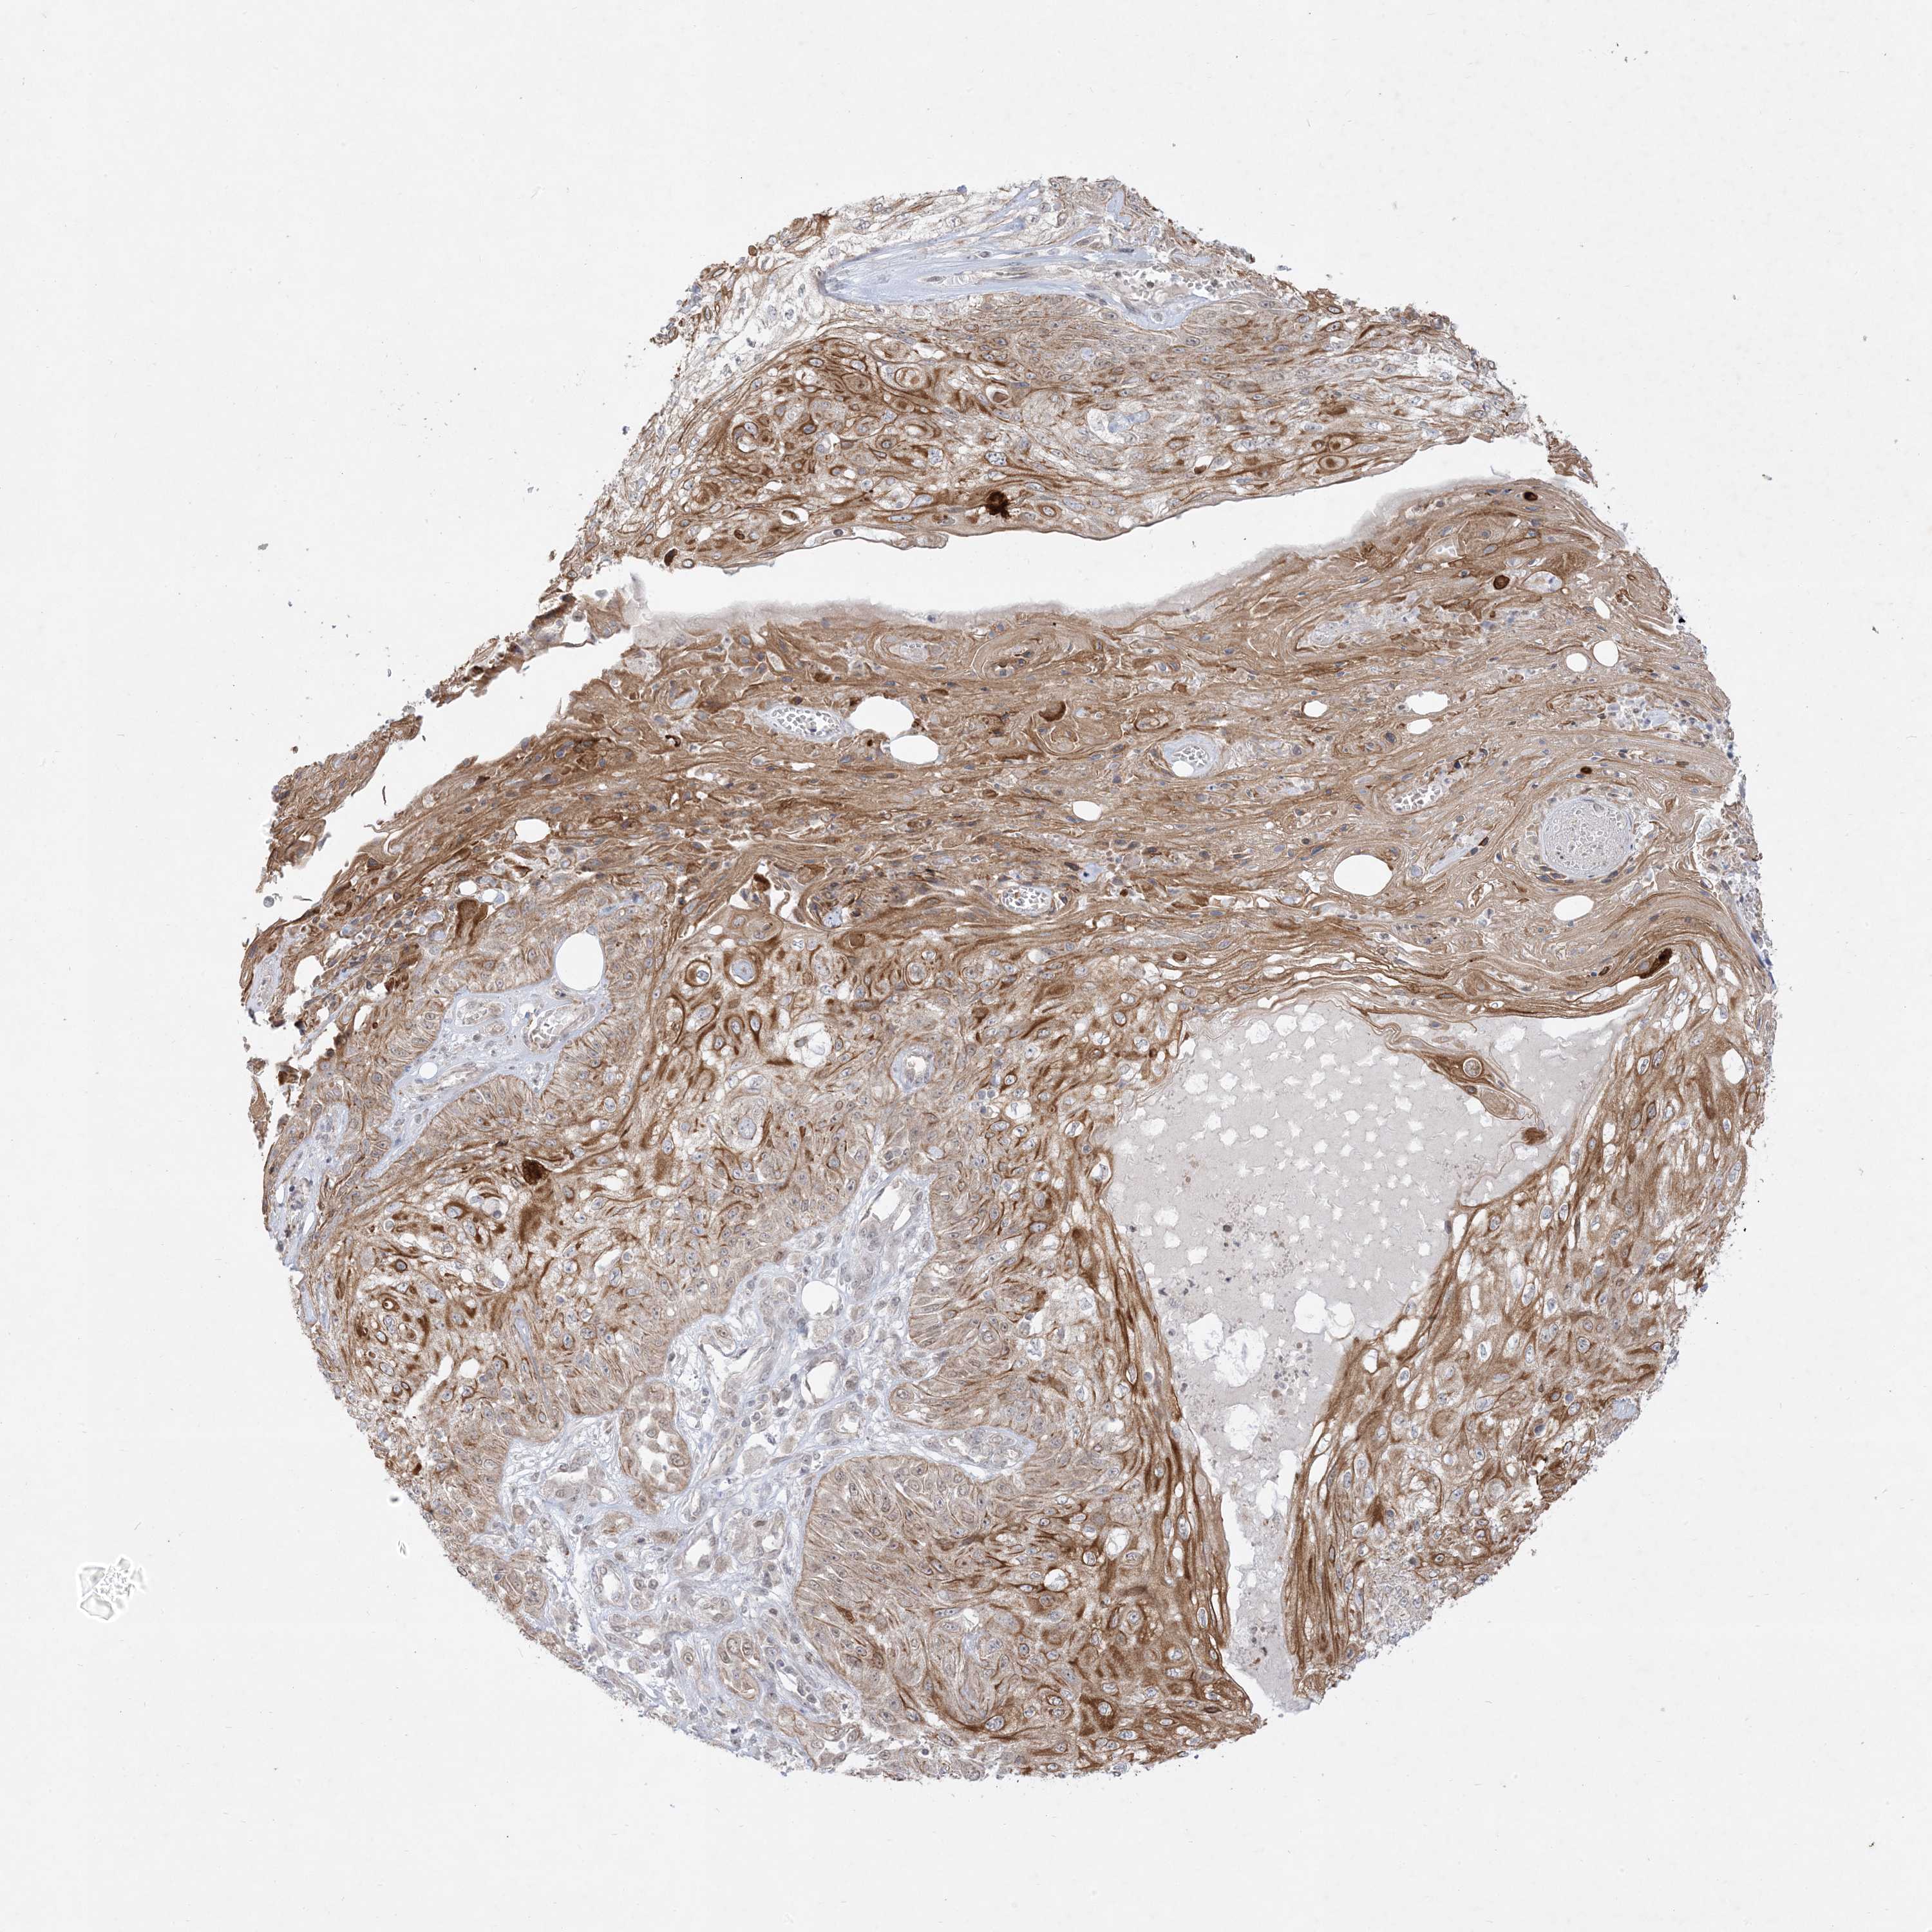

CANCER SKIN CANCER Show tissue menu

Basal cell and squamous cell cancer

SKIN CANCER - Protein expressioni

A mouse-over function shows sample information and annotation data. Click on an image to view it in a full screen mode. Samples can be filtered based on level of antibody staining by selecting one or several of the following categories: high, medium, low and not detected. The assay and annotation is described here.

Each image is clickable and will lead to virtual microscopy that enables deeper exploration of all samples and also displays staining intensity scores, fraction scores and subcellular localization as well as patient and tissue information for each sample.

Antibody HPA036070

Basal cell carcinoma

Squamous cell carcinoma, NOS

Squamous cell carcinoma, metastatic, NOS